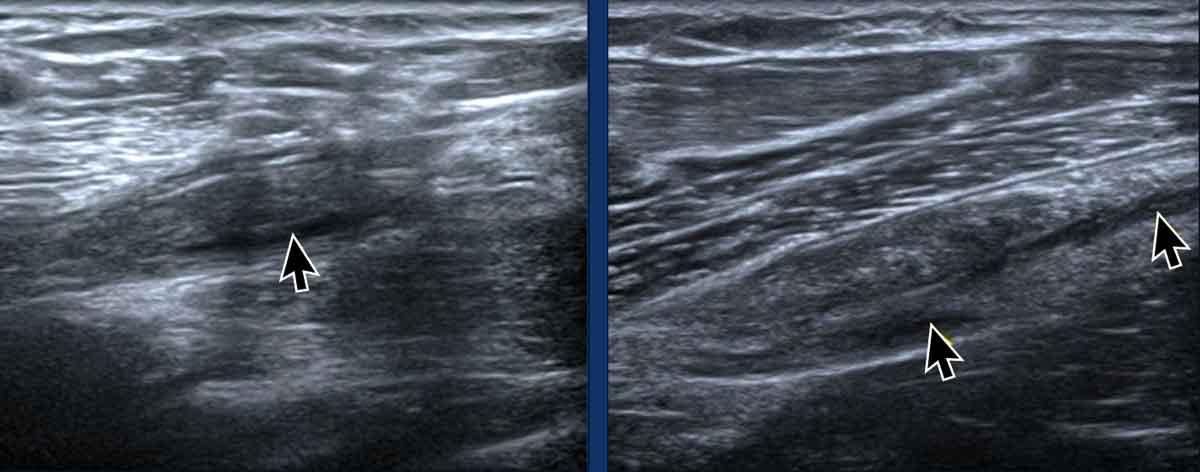

Tính dị hướng

Tính dị hướng là một artefact xảy ra khi chùm tia siêu âm không vuông góc với gân cơ nhị đầu dài (LHB). Sự lệch trục này dẫn đến giảm phản xạ sóng âm, gây mất độ phân giải và làm cho cấu trúc có hình ảnh tối, giảm âm (mũi tên đen). Trong một số trường hợp, điều này có thể tạo ra ấn tượng rằng gân LHB bị trật ra khỏi rãnh liên củ.

Để khắc phục hiện tượng dị hướng, hãy điều chỉnh lại vị trí đầu dò sao cho chùm siêu âm vuông góc với gân. Khi đó, gân cơ nhị đầu dài (LHB) sẽ lấy lại hình ảnh đặc trưng tăng âm, dạng sợi (mũi tên trắng).

Cần lưu ý rằng hiện tượng dị hướng cũng có thể ảnh hưởng đến các cấu trúc khác, chẳng hạn như gân cơ dưới vai trong hình ảnh này, tương tự cũng xuất hiện giảm âm do hiện tượng nhiễu ảnh này.